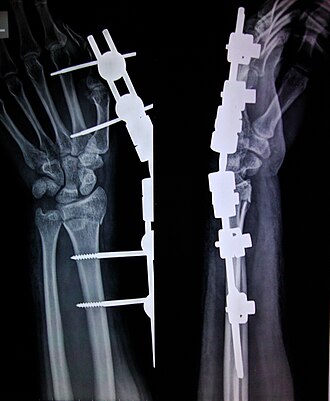

External Fixation involves placing metal pins or screws into the bone fragments on either side of a fracture, which are then connected to an external frame outside the body. This frame holds the bones in the correct position, ensuring stability as they heal.

• Pin Placement: Pins or screws are inserted through the skin into the bone on either side of the fracture.

• Frame Attachment: The pins are connected to a stabilising frame outside the body, which holds the bone fragments in alignment.

• Adjustment Capabilities: Many external frames can be adjusted to correct alignment as healing progresses.